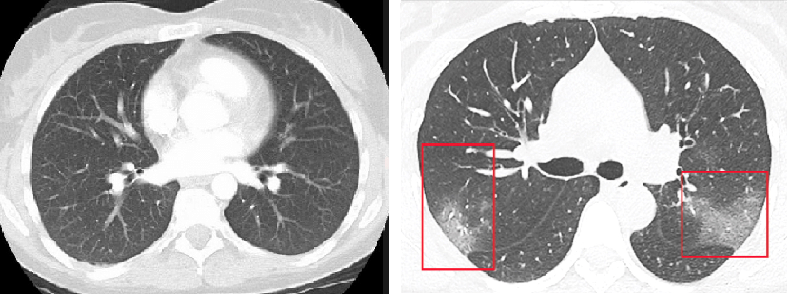

Nghiên cứu này và nghiên cứu của bác sĩ Xiao cho thấy khi bệnh tiến triển, ảnh CT cho thấy "các vệt thủy tinh mờ", một loại màng che ở các bộ phận của phổi có thể thấy rõ trong nhiều loại bệnh nhiễm trùng đường hô hấp do virus.

Những khu vực mờ đục đó có thể phân tán và dày lên khi bệnh nặng hơn, tạo ra thứ mà các bác sĩ chụp X-quang gọi là màng bao dày đặc trên máy quét.

Phổi trong giai đoạn đầu nhiễm bệnh (phải) và phổi khi virus bắt đầu tấn công (trái)